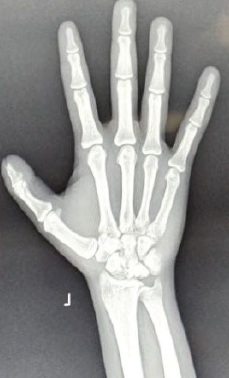

Functional Outcomes after Radial Shortening Osteotomy in Stage IIIA Kienböck’s Disease: A Five-Patient Case Series

Pramod Kumar , Salman Durrani , Abhinav Tiwari , Nischay Kaushik , Jashandeep Singh , Ritesh Kumar Sarraf

………………………………p.328-334